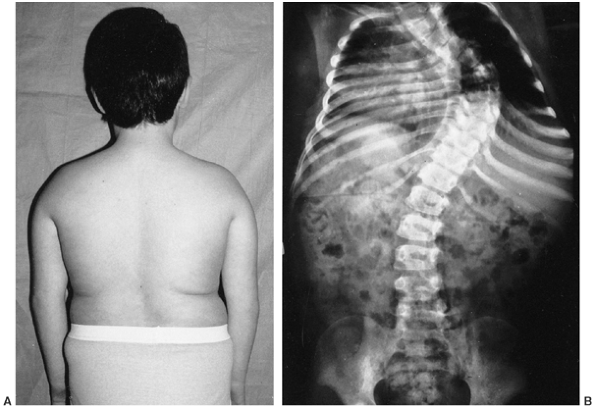

dysplastic (Fig. 9.3). The spinal deformity is

often associated with kyphosis, especially in the lumbar spine region.

Figure 9.3 Scoliosis (A, B) and protrosia of the hips (E) in a patient with Marfan syndrome. C, D:

Deformity of the apical vertebrae is shown in a three-dimensional reconstruction of a computerized tomographic scan image. (Courtesy of Chris Reily, MD, Vancouver, British Columbia, Canada.) |